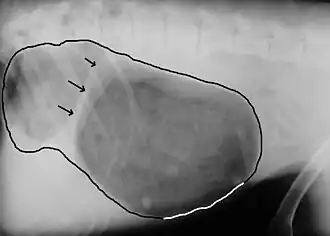

Eine relativ sichere Diagnose ist mit einer rechts anliegenden Röntgenaufnahme zu stellen, allerdings nur bei Drehungen um 180°. Dabei zeigt sich infolge der Aufgasung und Verlagerung der Erweiterung des Magenausgangs (Antrum pyloricum) – die in der überwiegenden Zahl der Fälle nach rechts, oben und vorn erfolgt – eine von vorn-unten nach hinten-oben verlaufende Falte. Dieses Phänomen bezeichnet man auch als „Kompartmentbildung“, sie verleiht dem Magen ein „zipfelmützenartiges“ Aussehen. Im englischen Sprachraum wird dies als „double bubble“ („Doppelblase“) bezeichnet. Beim Vorliegen einer Kompartmentbildung kann eine Magendrehung bereits sicher von einer einfachen Magenüberladung abgegrenzt werden. Bei der – allerdings sehr seltenen – Drehung gegen den Uhrzeigersinn ist sie jedoch nicht zu beobachten. Bei einer linksanliegenden Röntgenaufnahme ist die Kompartmentbildung generell nicht nachzuweisen. Bei rückenseitiger Lagerung stellt sich das – normalerweise rechts liegende – Antrum pyloricum links der Mittellinie dar. Weitere Kriterien sind eine Verlagerung des Darmes und der Milz nach hinten sowie die in manchen Fällen auftretende Verjüngung der hinteren Hohlvene (Vena cava caudalis) am Zwerchfelldurchtritt infolge eines Schocks. Bei schweren und länger bestehenden Magendrehungen, die bereits zu einem Absterben der Magenwand geführt haben, kann sich Gas in der Magenwand (Emphysem) darstellen, dann ist die Heilungsaussicht bereits schlecht.[9] Bei Drehungen um 360° ist die diagnostische Sicherheit deutlich geringer. In einer Studie aus dem Jahr 2025 lag die Erkennungssicherheit selbst bei geprüften Radiologen nur bei etwa 50 %.[10]